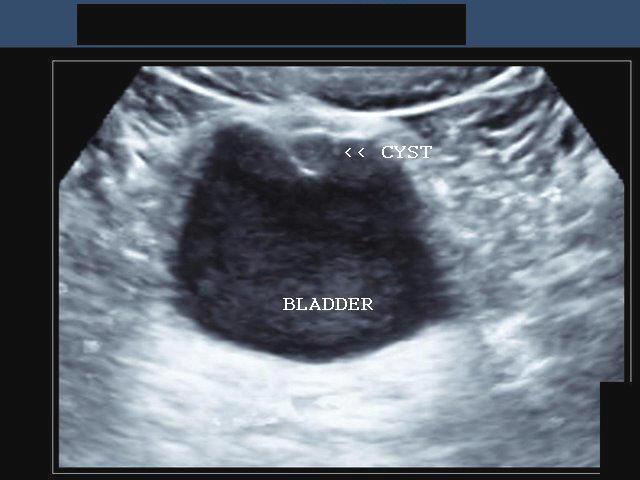

Urachal fistula

Urachal fistula

What is a urichal fistula?

Urachus doesn't close and belly button leaks urin

Urachal cyst

Urachal cyst

Urachal cyst